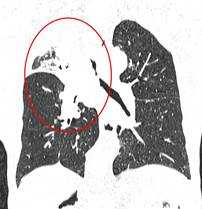

Фото 2 — Периферический рак (1) верхней доли правого легкого

Периферический рак легких на КТ выглядит как очаг либо узел, расположенный на периферии органа вдалеке от корня. Обычно он имеет однородную структуру, в некоторых случаях с участками некроза, обызвествлениями и кровоизлияниями в паренхиму. Края типичной раковой опухоли неровные, с множественными «спикулами» за счет лимфангиита. При расположении вблизи плевры образование деформирует ее и подтягивает к себе. Размеры его различны - от очага (3-10 мм) до узла (10-50 мм и больше).

Типичный периферический рак легкого (аденокарцинома) на МСКТ. Справа в 6 сегменте легкого выявлен плотный мягкотканный узел со спикулами, деформирующий и подтягивающий к себе междолевую плевру.